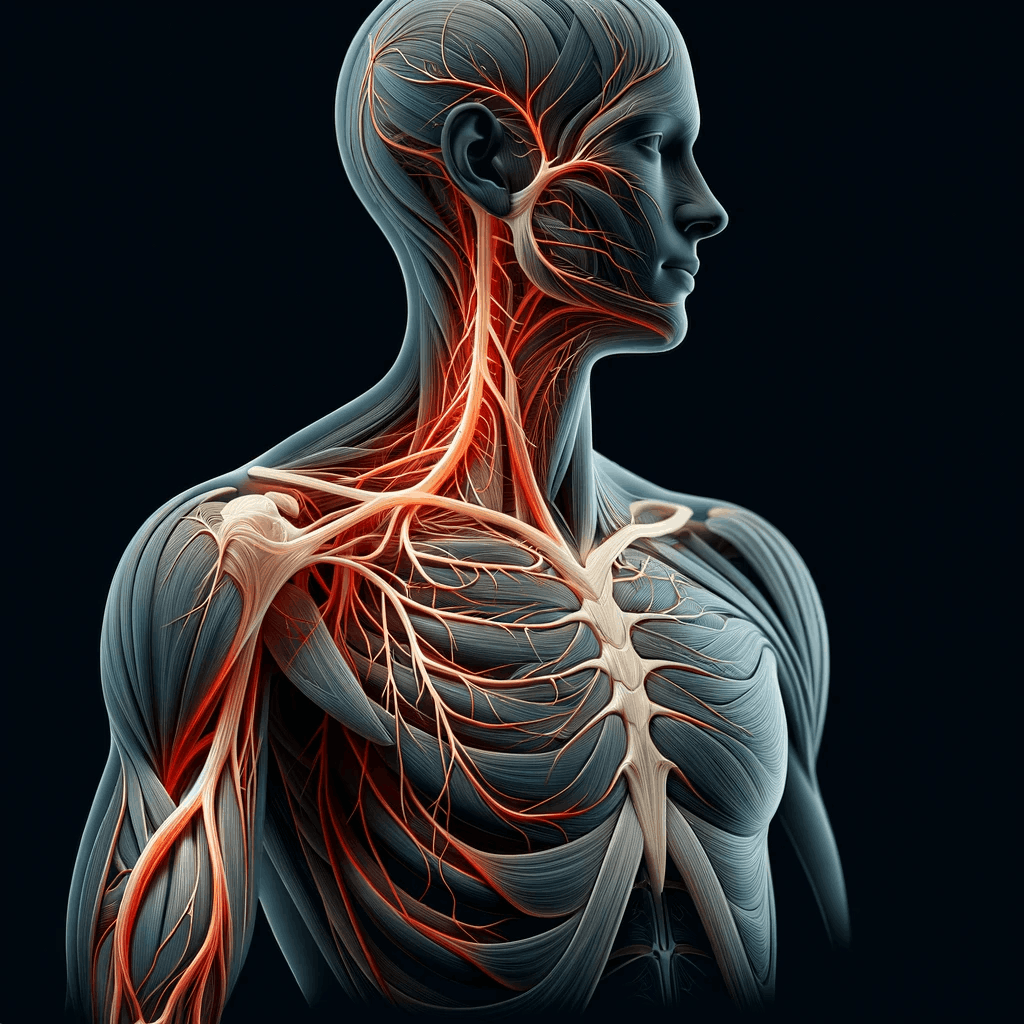

Symptoms of a herniated disc at C5-C6 can vary, but they often include a distinct pattern of discomfort and physical limitations.

Patients may experience pain radiating from the neck down to the shoulder, arm, and even into the fingers, typically on one side of the body.

This pain can be accompanied by numbness, tingling, or weakness in the affected arm and hand.

The susceptibility of the C5-C6 disc to injury is not just a matter of its location.

This segment endures significant stress due to its role in supporting the head and facilitating neck movements.

Repetitive motions, poor posture, and the natural aging process can all contribute to the wear and tear of this disc.